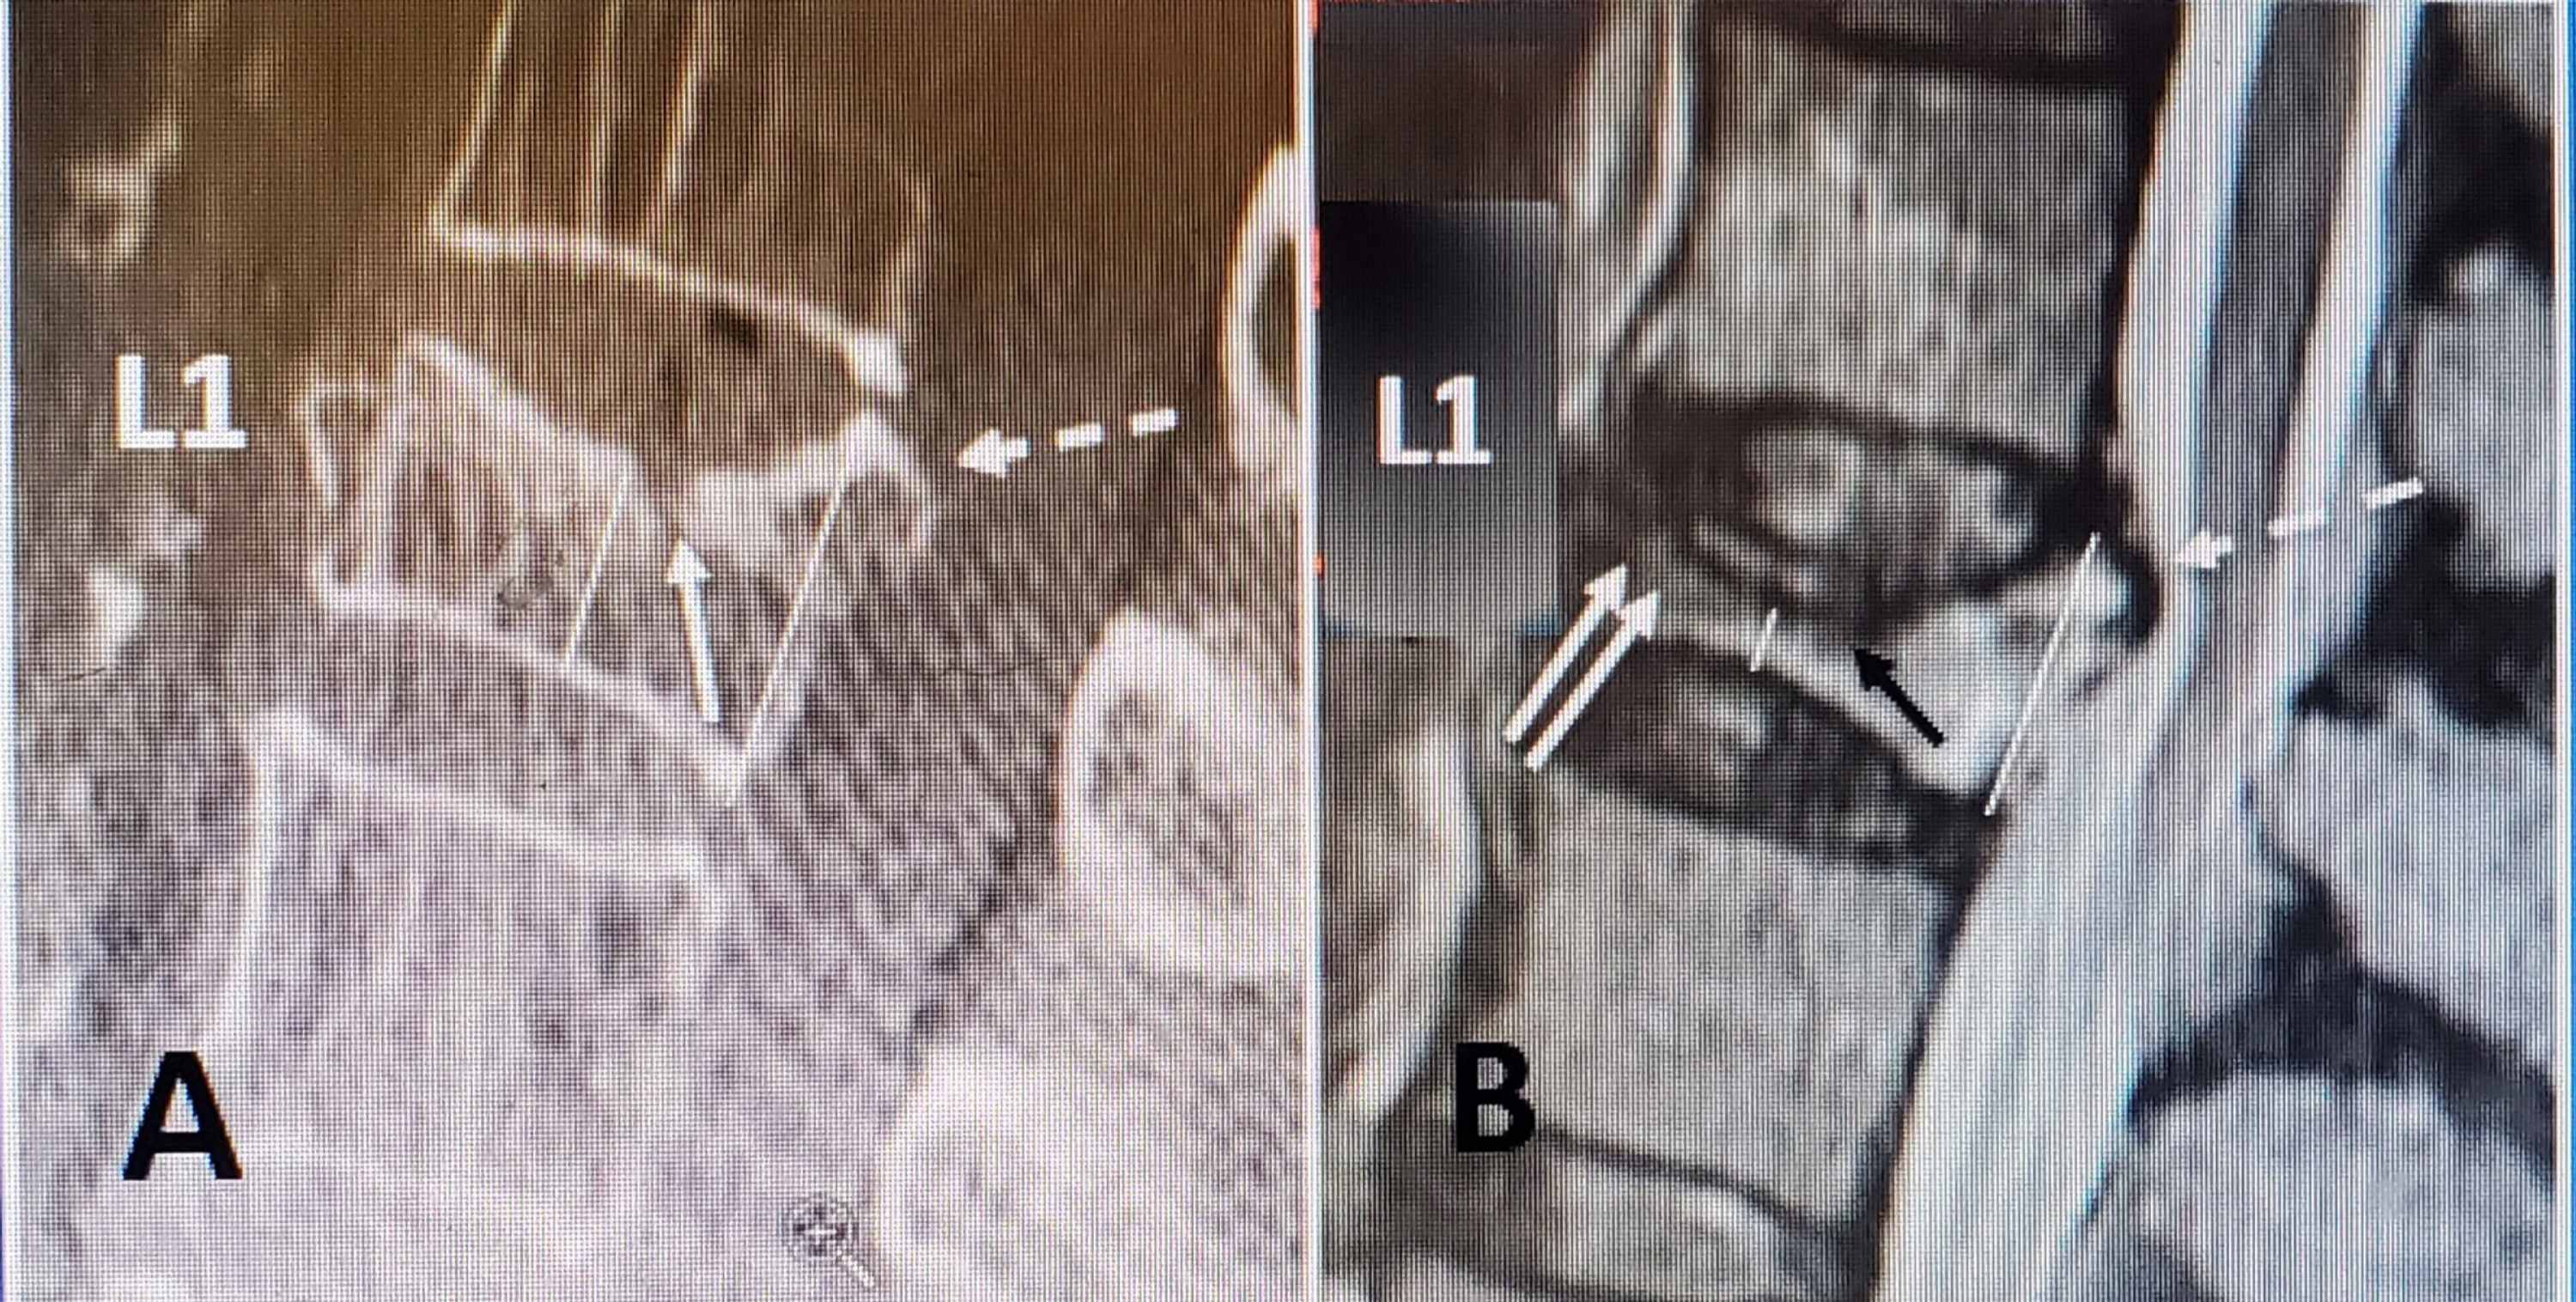

Imaging studies after the Spine‐Jack® procedure. (A, B) CT and

Spine Jack Procedure spinejack system procedure | interventional spine. spinejack system instructions for use. the spinejack system offers three implant kit sizes: overview two unexpanded implants are inserted into the fractured vertebral body.7 implants are slowly expanded, allowing. You can get up to 12 months of relief with spinejack. spinejack is a system that treats osteoporotic vertebral compression fractures, the most common cause of severe back pain. Through bipedicular access and a series of cannulated. spinejack system procedure | interventional spine. Each kit contains the appropriate. the spinejack system allows you to take full control of implant placement and expansion. Pain doesn't have to be permanent. the spinejack ® system is indicated for use in the reduction of mobile spinal fractures that may result from osteoporosis, trauma. spine jack kyphoplasty is a minimally invasive surgery that uses a titanium implant to restore height and.